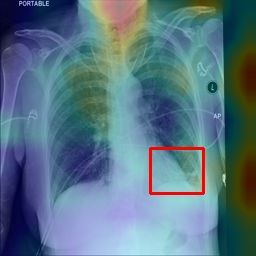

Deployments of artificial intelligence in medical diagnostics mandate not just accuracy and efficacy but also trust, emphasizing the need for explainability in machine decisions. The recent trend in automated medical image diagnostics leans towards the deployment of Transformer-based architectures, credited to their impressive capabilities. Since the self-attention feature of transformers contributes towards identifying crucial regions during the classification process, they enhance the trustability of the methods. However, the complex intricacies of these attention mechanisms may fall short of effectively pinpointing the regions of interest directly influencing AI decisions. Our research endeavors to innovate a unique attention block that underscores the correlation between 'regions' rather than 'pixels'. To address this challenge, we introduce an innovative system grounded in prototype learning, featuring an advanced self-attention mechanism that goes beyond conventional ad-hoc visual explanation techniques by offering comprehensible visual insights. A combined quantitative and qualitative methodological approach was used to demonstrate the effectiveness of the proposed method on the large-scale NIH chest X-ray dataset. Experimental results showed that our proposed method offers a promising direction for explainability, which can lead to the development of more trustable systems, which can facilitate easier and rapid adoption of such technology into routine clinics. The code is available at www.github.com/NUBagcilab/r2r_proto.